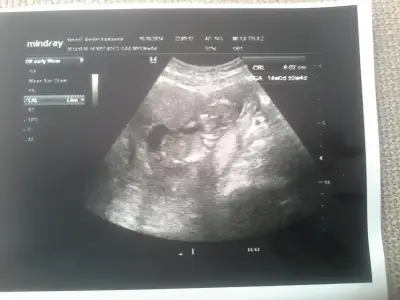

Diğer ultrason görüntülerini atıyorum, lütfen bide bunlara bakarmısın?

Eki Görüntüle 1277161 Eki Görüntüle 1277162

Canim bebisimin fotosunu attim bakarmisin dr soylemiyo erken diyo galiba goruyo ama simdi soylemek olmaz diyo rica etsem siz ne goruyorsunuz ben anlamadim su nub olayinisayfa yöneticisi yurt dışından o yüzden ulaşılamıyo pek yine de bi sorayım